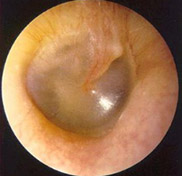

Notice the different shades of color yet the eardrum still remains an opaque translucent appearance in all the pictures

These images are for informational purposes only unless you are a physician or clinician who might use them as part of their medical training. Please remember only your Doctor can make a diagnosis of a medical problem. It is important to ALWAYS SEEK MEDICAL ATTENTION for any MEDICAL CONDITION. We have purposely shown more than one picture representing the same condition. You will find in the real world of eardrums that no two look exactly alike. This is why it is important to practice doing ear exams with your otoscope on as many willing volunteers as you can to get a feel for what is usual and normal. Also please realize these photos were taken with a $3,000 high resolution video otoscope so what you see with a standard hand held otoscope during an exam of an ear canal can not be expected to be as clear.